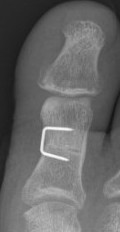

Akin osteotomy

Indications

- hallux interphalangeus > 10o

Technique

- medial closing wedge osteotomy of P1